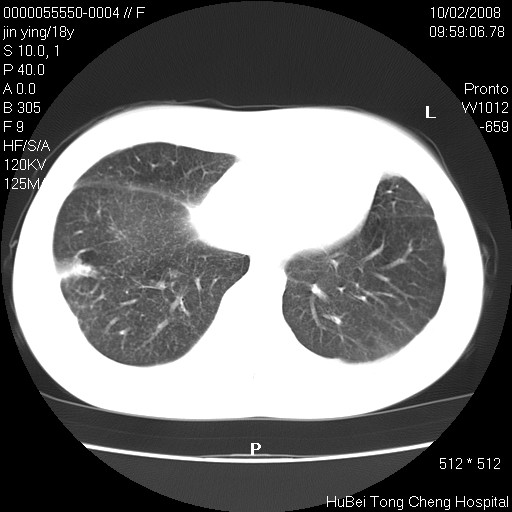

患者 女,18y。发热十余天,伴咳嗽。pe:t39⒈℃,bp 110/80mmhg,p 86次/min。神清,精神欠佳。双肺可闻及少许湿罗音。既往史不详。

临床诊断:肺部感染?

胸部ct轴位平扫(层厚10mm,螺距1.5,重建间隔10mm),图像如下: